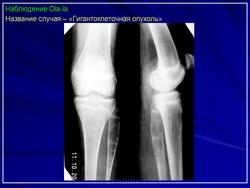

Гигантоклеточная опухоль.